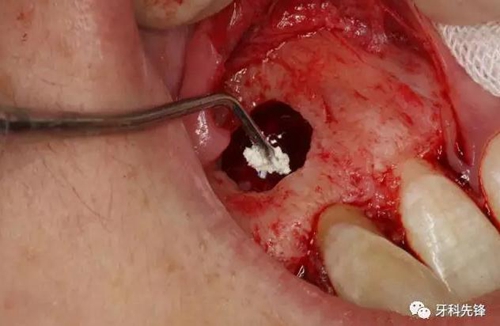

圖11.取出囊腔內(nèi)的致密團(tuán)塊。

圖12. 取出沒有完全鈣化形成的牙齒。

圖13.摘除囊壁。

圖14.摘除后的囊腫情況,并用超聲骨刀清理根尖區(qū)后,可清晰看到12牙根未發(fā)育,根管粗大開放。

圖15.開放的根尖區(qū)用MTA封閉。